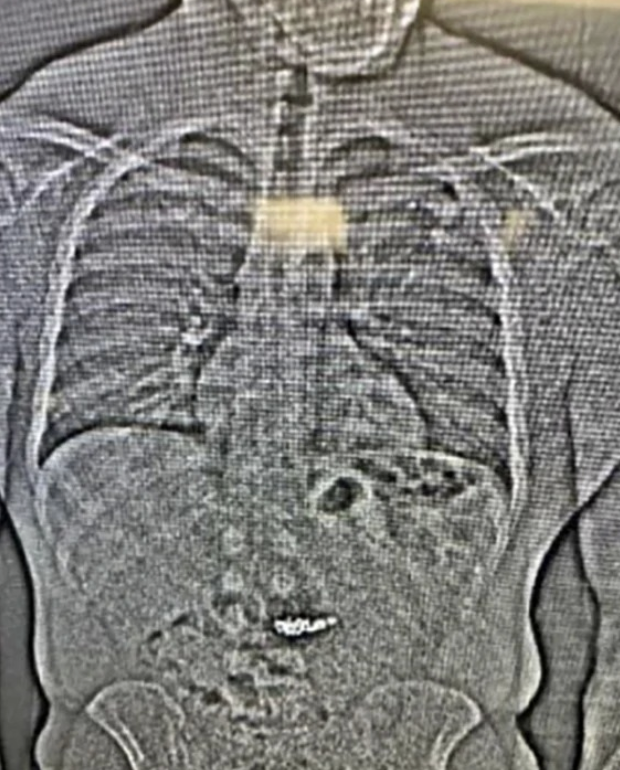

An X-ray of his torso shows what the Orlando Police Department believed to be the diamond earrings — a white mass shining brightly against the gray backdrop of his digestive tract.

"These foreign objects are suspected to be the Tiffany & Co earrings taken in the robbery but will need to be collected ... after they are passed," the department's arrest report said.

This image provided by the Orlando Police Department shows an x-ray of what are believed to be two diamond earrings that were stolen from a Tiffany & Co. jewelry store in central Florida and were swallowed by the suspect.